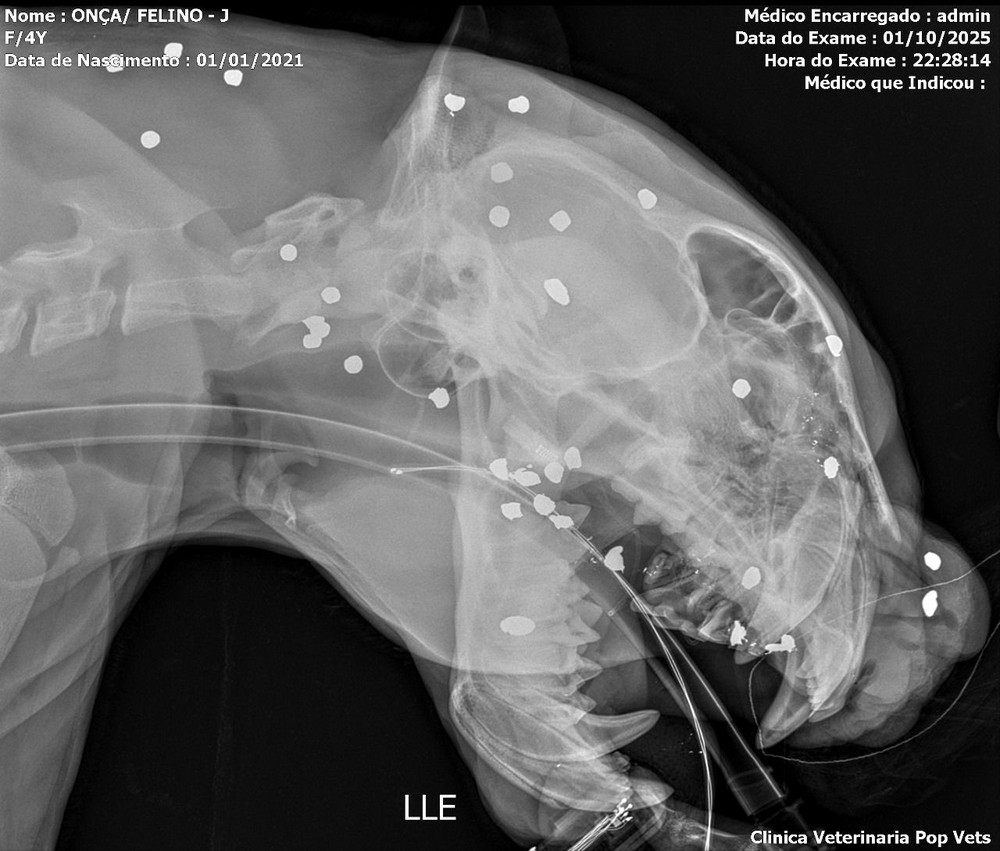

엑스레이 검사 결과 얼굴 머리 목에 샷건 총알이 30개 이상 박혀있었다고 함

산탄총을 멀리서 쏴서 저리 많이 박혀도 살아남은듯